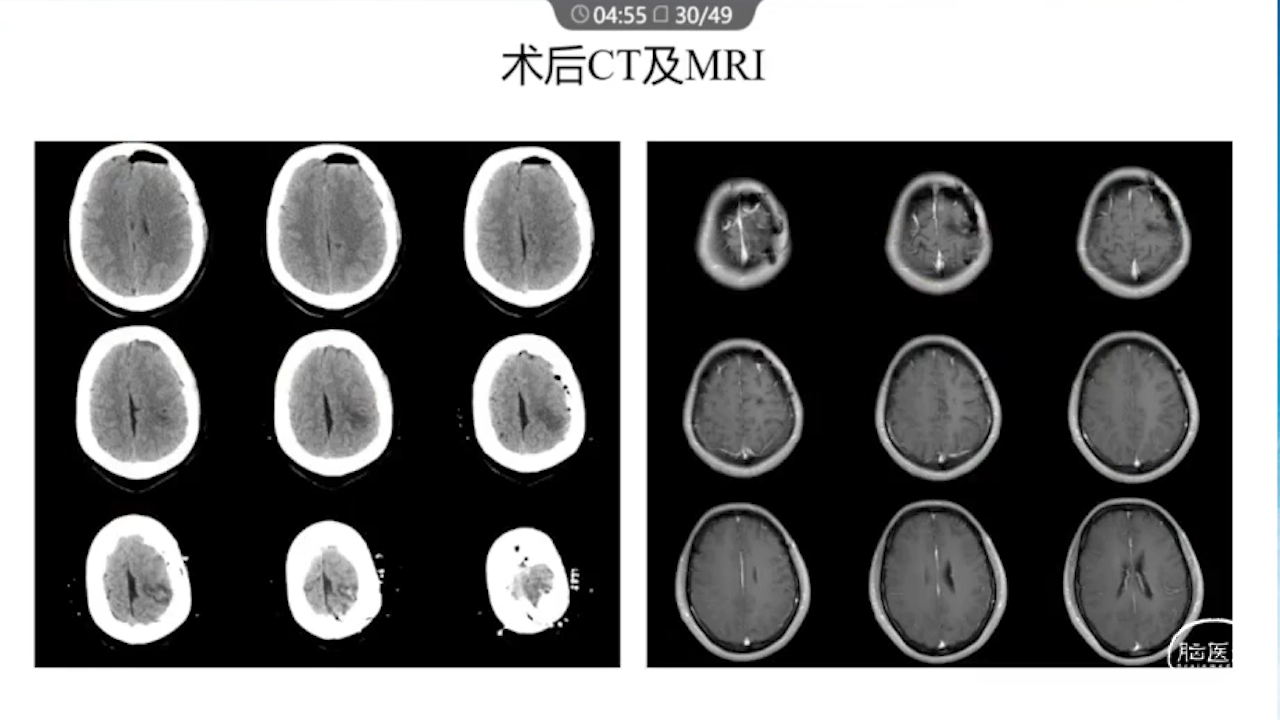

1、术前需要完善的影像学检查、多模态融合及神经导航以进行精确的肿瘤及静脉血管定位。

7、术中辅助技术:实时定位并保护静脉,监测其通畅性(荧光造影、Flow800)。

8、术后积极进行脱水治疗:如果术后脱水不及时,将可能发生严重的脑水肿,导致功能区脑组织受压、静脉回流障碍等一系列的严重反应。